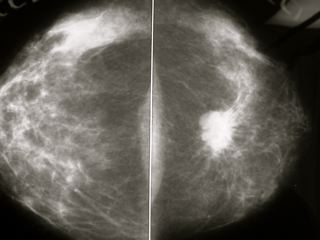

Detección del cáncer de mama mediante mamografía, tomosíntesis mamaria digital y resonancia magnética según la densidad mamaria

28 agosto 2024

En este análisis de efectividad comparativa basado en modelos, la resonancia magnética suplementaria para mujeres con mamas densas sumada al cribado con mamografía condujo a mayores beneficios y también mayores daños. El balance de esta compensación para el uso de RMN suplementaria fue más favorable cuando se dirigió a mujeres con mamas extremadamente densas que comprenden aproximadamente el 10% de la población. JAMA Internal Medicine, 26 de agosto de 2024.